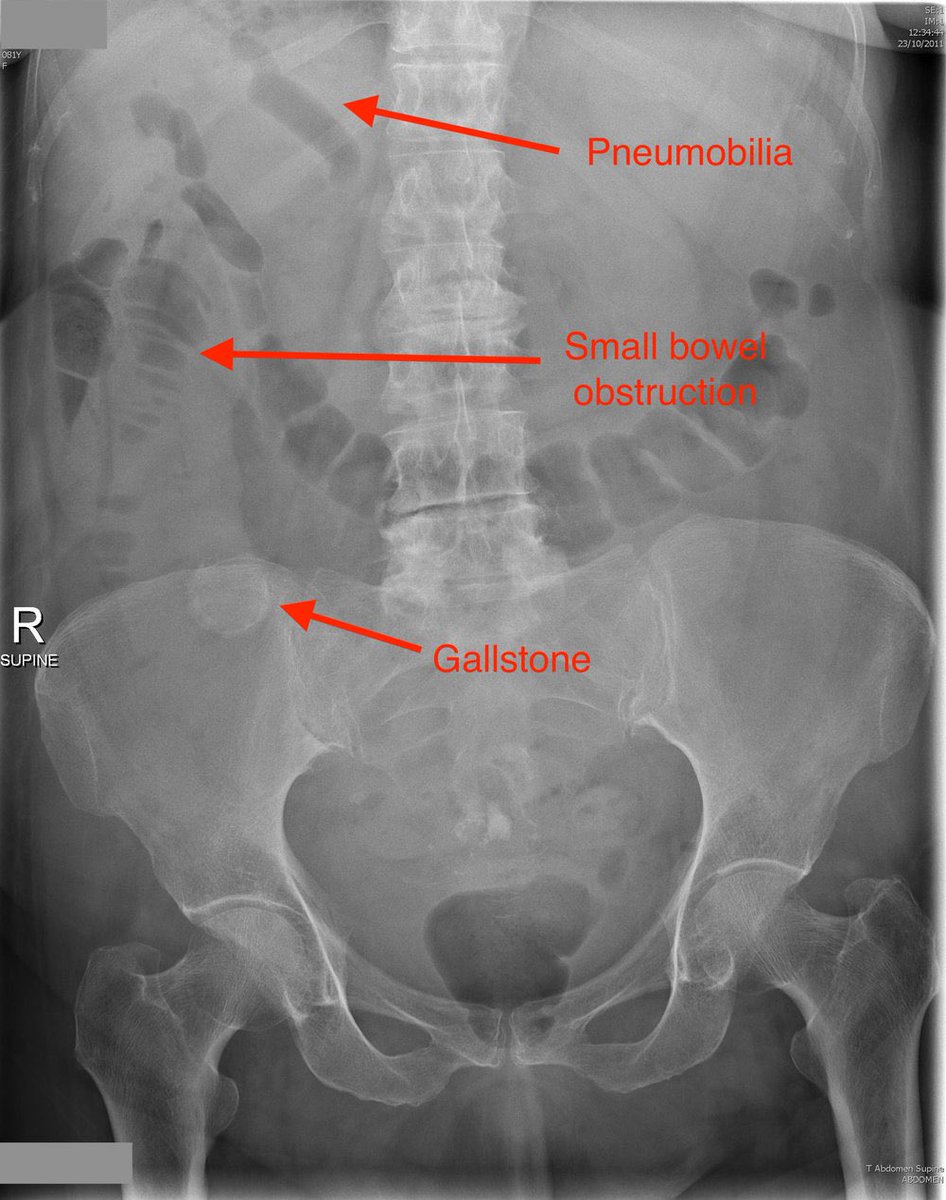

4-Rigler Triad (gall stone ileus)

1️⃣small bowel obstruction

2️⃣Air in biliary tree 🌳

3️⃣Stone in the right lower quadrant